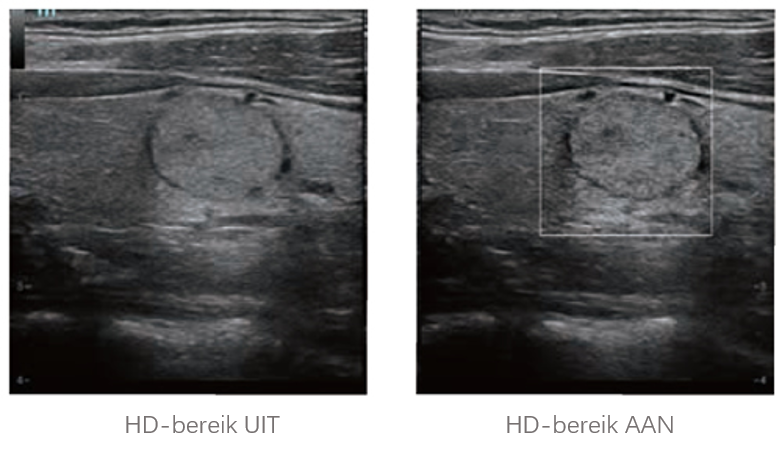

Sinds de oprichting van het bedrijf is Mindray voortdurend op zoek naar nieuwe manieren om het diagnostisch vertrouwen te vergroten. Resona 7 wordt aangestuurd door de meest revolutionaire ZONE Sonography?-technologie. Zijn nieuwe ZST+-tilt de kwaliteit van ultrasoundbeeldvorming naar een hoger niveau door middel van zoneacquisitie en kanaalgegevensverwerking.